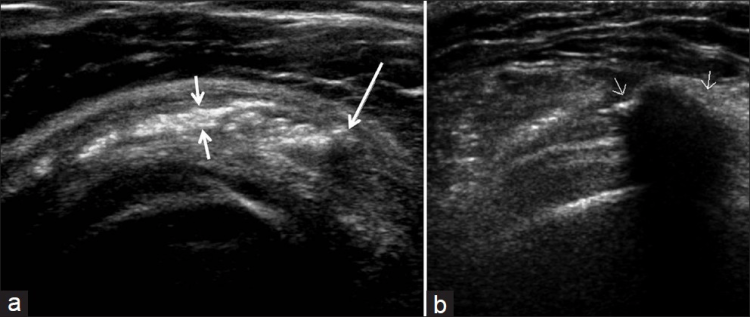

Los desgarros del manguito de los rotadores son la patología más común que se encuentra en los exámenes de ultrasonido del hombro.[7] La incidencia de lágrimas aumenta con la edad. Los desgarros de tendones se pueden clasificar de acuerdo con el grado de falla de la fibra, que van desde desgarros completos [Figura 7], desgarros de espesor total [Figuras 8, 9], desgarros de espesor parcial [Figuras 10-12] y desgarros intrasustancia [Figura 13 ]. Un desgarro agudo suele ir acompañado de derrame articular o bursal [Figura 12]. [7-9] La ausencia de derrame generalmente se relaciona con desgarros crónicos.[9] En un metanálisis sobre la precisión de la resonancia magnética, la artrografía por resonancia magnética y la ecografía en el diagnóstico de desgarros del manguito de los rotadores, la ecografía ofreció una alta sensibilidad y especificidad para la evaluación de los desgarros del manguito de los rotadores de espesor total (92,3 y 94,4 %, respectivamente) con 85,1 % y 92 %, respectivamente para todas las lágrimas.[7] El desgarro de espesor parcial aparece como un defecto o hendidura hipoecogénica en el tendón, afectando solo una parte de su espesor, mientras que un desgarro de espesor total se extiende desde la bolsa hasta la superficie articular del tendón. Un desgarro completo es un desgarro de espesor completo que afecta todo el ancho del tendón. El tendón se retrae medialmente, y la cantidad de retracción depende de la edad del desgarro. En las roturas crónicas, el tendón desaparece por debajo del arco coracoacromial, dejando la cabeza humeral descubierta por el supraespinoso, el denominado signo de la "cabeza desnuda". Los hallazgos de la ecografía incluyen la falta de visualización del tendón y la hernia del músculo deltoides. Los desgarros intrasustancia permanecen localizados en el tendón sin afectar sus márgenes. Los desgarros intrasustancia y de espesor parcial pueden ser difíciles de diferenciar de la tendinopatía focal.

Las patologías no relacionadas con desgarros del manguito rotador que se encuentran con más frecuencia son la tendinosis del manguito rotador [Figura 14], la tendinitis calcificante del manguito rotador [Figura 15] y el pinzamiento del tendón subacromial [Figura 16]. Vale la pena señalar que, en tales casos, se pueden desarrollar desgarros debido a la debilidad del tendón [Tabla 2].[79] La tendinosis o tendinopatía del manguito de los rotadores se presenta como inflamación del tendón con una ecotextura hipoecoica heterogénea del tendón. Las calcificaciones del manguito de los rotadores aparecen como focos hiperecogénicos, ya sea con una sombra posterior bien definida (Tipo I) o con una sombra tenue (Tipo II) o ausente (Tipo III). El Tipo I corresponde a la fase formativa y los Tipos II y III a la fase de reabsorción, en la que cambian a depósitos de calcio semi o totalmente líquidos. En el pinzamiento subacromial, el tendón no se desliza en el espacio subacromial durante la abducción y la elevación anterior del brazo.